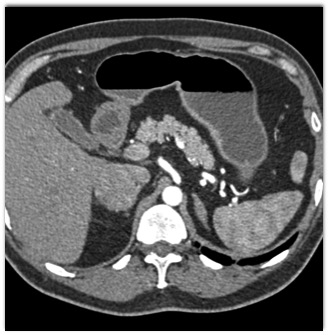

The most likely diagnosis of the right adrenal mass is?

hematoma

pheochromocytoma

metastatic renal cell carcinoma

primary adrenal cortical carcinoma